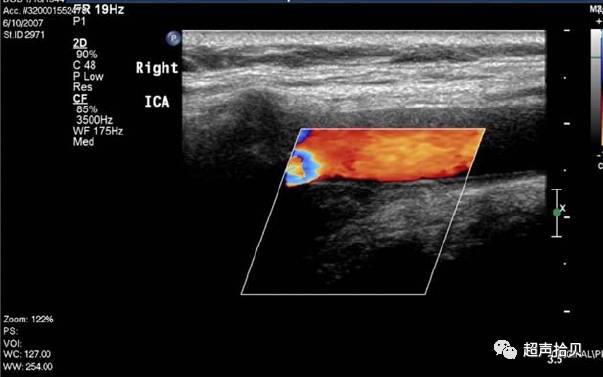

图3,女,71岁;颈总动脉A,远端低回声增厚。 B,彩色多普勒在局灶性增厚中没有显示可检测的血流的;ICA 颈内动脉